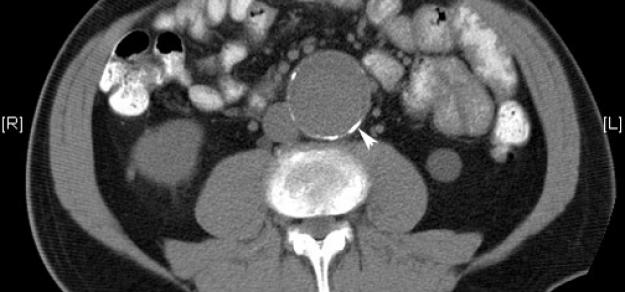

Heart, 1 de abril de 2019 la prescripción de metformina podría limitar la expansión de la AAA entre los pacientes con esta enfermedad, y podría estar involucrada con una menor incidencia de aneurisma aórtico y eventos de aneurisma aórtico